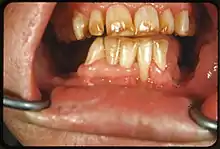

Dents colorées par le fluor chez un patient vivant à Deming (Nouveau-Mexique) dans une zone connue pour ses fluoroses endémiques.